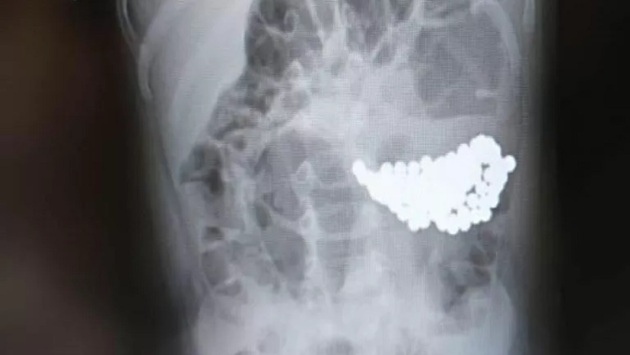

В Волгограде врачи спасли девочку, которая проглотила 134 магнитных шарика.

После обследования выяснилось, что причиной недомогания стала кишечная непроходимость, вызванная большим скоплением инородного тела. Магнитные шарики вызвали конгломерат, который сдавливал стенки кишечника.

Благодаря слаженной работе волгоградских специалистов, была проведена успешная лапароскопическая операция по извлечению магнитов. Сейчас состояние девочки стабильное.